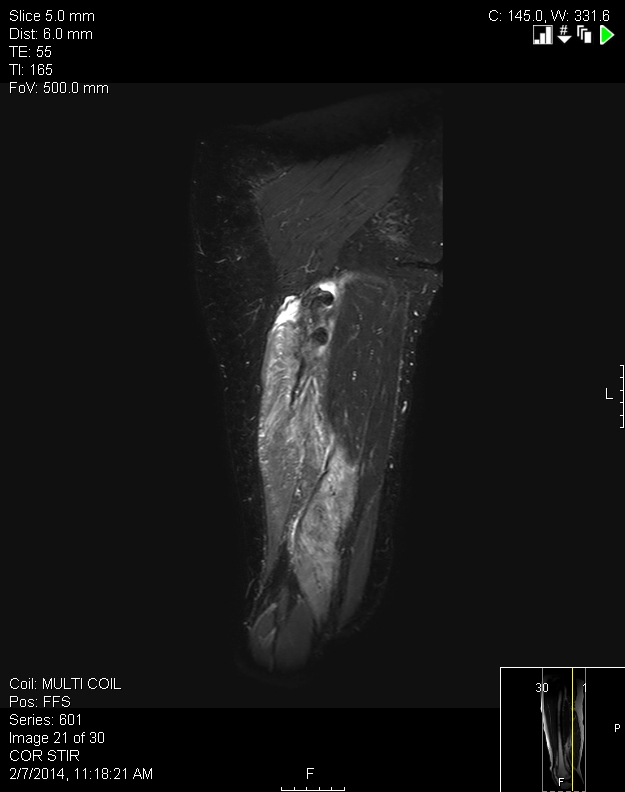

From www.semanticscholar.org

Total proximal hamstring ruptures clinical and MRI aspects including Hamstring Knot If your glutes are weak, hamstrings can be overloaded. Find out the anatomy, function. A hamstring tear injury is a rip in the hamstring muscles. hamstrings often become tight due to injury—most commonly a hamstring strain. your glutes are weak. There might also be a popping. Glutes and hamstrings work together. a hamstring injury typically causes a. Hamstring Knot.